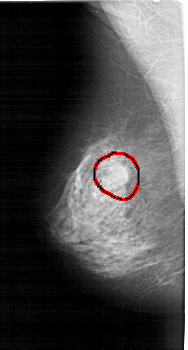

FILE: A_1396_1.LEFT_CC.OVERLAY

TOTAL_ABNORMALITIES 1

ABNORMALITY 1

LESION_TYPE MASS SHAPE ROUND MARGINS OBSCURED

ASSESSMENT 4

SUBTLETY 3

PATHOLOGY BENIGN

TOTAL_OUTLINES 1

BOUNDARY